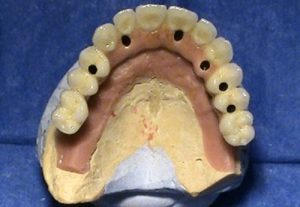

3. PHASE – prosthetic fabrication of temporary crown on implant

3. PHASE – fabrication of temporary solution